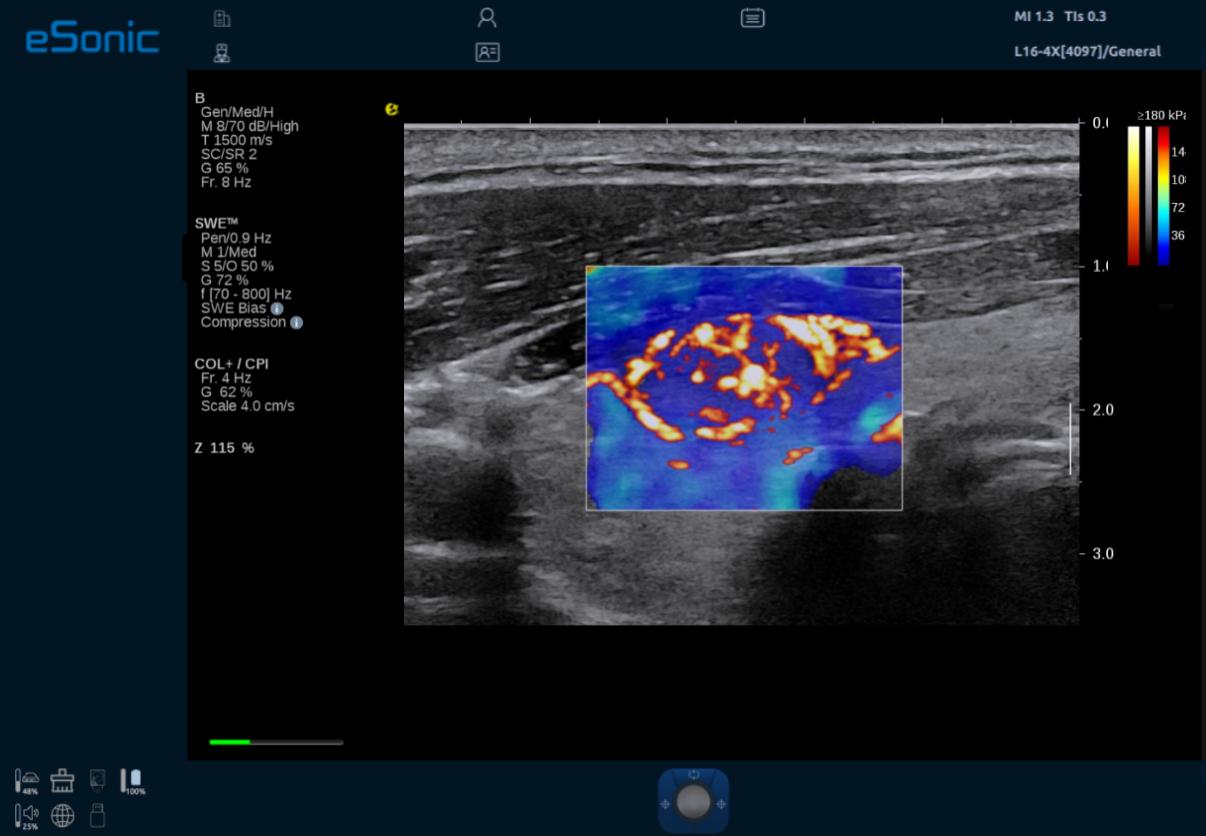

eTriplex 弹性三同步成像